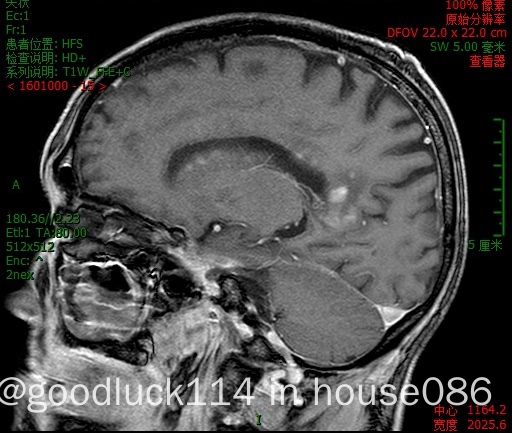

高龄取不了病理,医院做不了pet-ct,做了头颅ct和mri,发现颅内占位性病变,怀疑原发或转移,但胸部ct腹部ct和肿瘤标志物都没有明显异常,也没有除神经系统外其他系统的症状,mri增强结果不像是胶质瘤,高度怀疑是原发性中枢淋巴瘤。